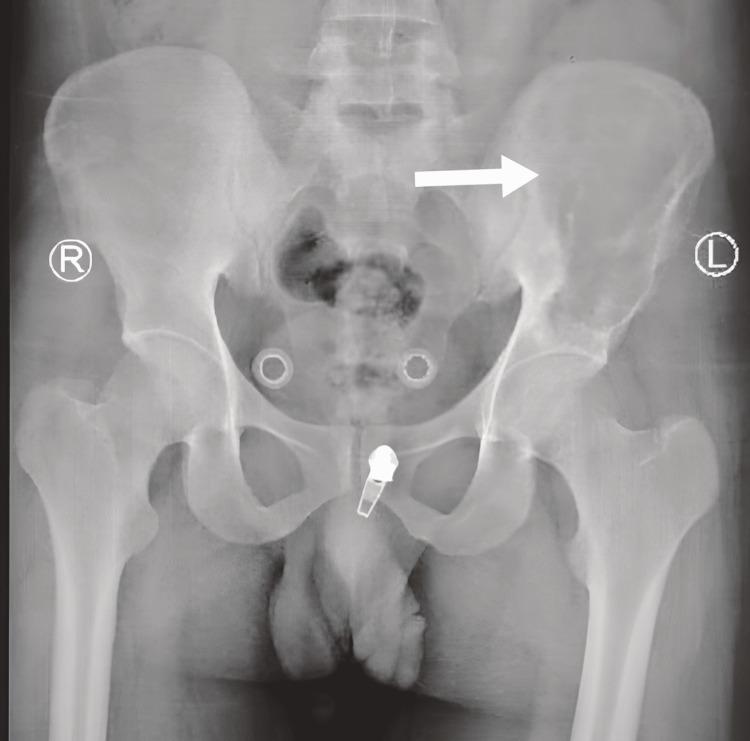

Lytic bone lesions pose significant diagnostic challenges due to their varied causes, ranging from malignancies to infections and benign conditions. Tuberculous osteomyelitis, though rare in non-endemic regions, remains an important consideration, particularly in patients from high-burden areas. A 35-year-old Sudanese male with a family history of tuberculosis (TB) presented with chronic left iliac pain that did not respond to nonsteroidal anti-inflammatory drugs (NSAIDs). Imaging revealed an expansile lytic lesion with cortical breaching, initially raising suspicion for malignancy. However, a biopsy showed necrotizing granulomatous osteomyelitis, though cultures - including those for were negative. Despite the lack of microbiological confirmation, the patient showed clinical and radiological improvement after starting empirical anti-TB therapy. This case highlights the need to consider tuberculous osteomyelitis in the differential diagnosis of lytic bone lesions, even in the absence of positive cultures, especially in individuals from endemic regions. Histopathological evidence of granulomas and a positive response to anti-TB therapy can support the diagnosis when microbiological tests are inconclusive. Greater awareness of this possibility is essential to prevent delays in treatment and unnecessary invasive procedures.

溶骨性骨病变因其病因多样,从恶性肿瘤到感染及良性疾病,带来了重大的诊断挑战。结核性骨髓炎在非流行地区虽罕见,但仍是一个重要的考虑因素,尤其是在来自高负担地区的患者中。一名35岁有结核病家族史的苏丹男性,出现慢性左髂骨疼痛,对非甾体抗炎药无反应。影像学检查发现一个有皮质破坏的膨胀性溶骨性病变,最初怀疑为恶性肿瘤。然而,活检显示为坏死性肉芽肿性骨髓炎,尽管包括结核菌培养在内的培养结果均为阴性。尽管缺乏微生物学确诊依据,但患者在开始经验性抗结核治疗后临床和影像学表现有所改善。该病例强调,即使在培养结果为阴性的情况下,在溶骨性骨病变的鉴别诊断中也需要考虑结核性骨髓炎,特别是在来自流行地区的个体中。当微生物学检查结果不明确时,肉芽肿的组织病理学证据及对抗结核治疗的阳性反应可支持诊断。提高对这种可能性的认识对于防止治疗延误和不必要的侵入性操作至关重要。